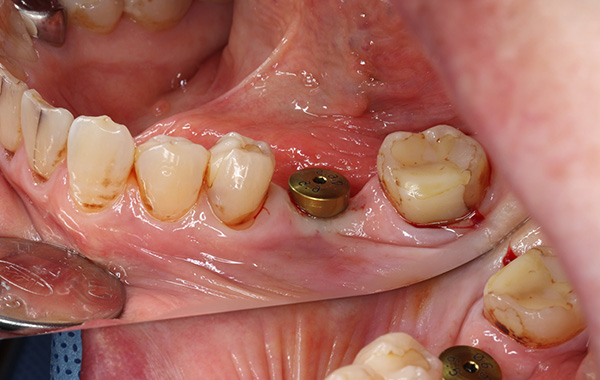

インプラント埋入

右下の奥歯にインプラント希望で来院されました。

骨の量も幅も十分であったため、患者様にフラップレスでのオペをおすすめしたところ、希望されたため行いました。

オペ自体も30分もかからず終了し、縫合もないので、術後の痛みもほぼなく、翌日には痛み止めを飲まずに来院されました。

主訴 右下にインプラントを

入れたい

治療期間 4ヶ月

治療費 440,000円

治療内容 右フラップレスインプラントで術後の痛みは

全くないとおっしゃっていました。